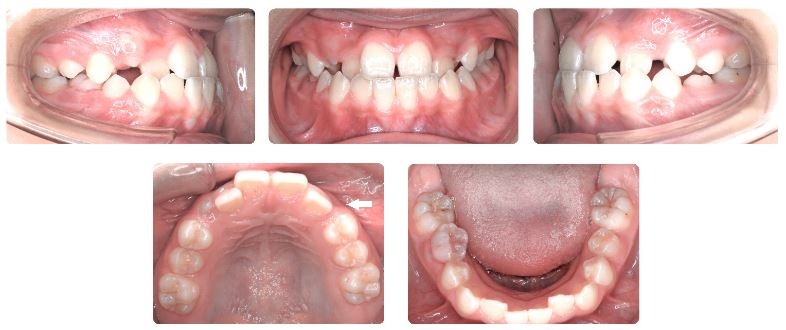

診断名:前歯部叢生を伴う反対咬合

前歯の歯並びを治したいとのことで来院されました。

上あごの歯列幅が狭く、矢印で示す箇所のように左側の犬歯の生えるスペースが足りない状態です。

前歯の噛み合わせが浅めの反対咬合のケースですが、骨格的な因子はそれほど強くないため下顎の成長方向のコントロールや上顎前方牽引は必要ありませんでした。